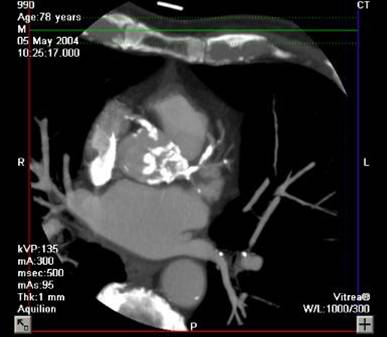

The non-invasive imaging modality of multi-detector computed tomography has dramatically evolved the last ten years and that is due to hardware and software developments. The newer generation of scanners allows increased spatial and temporal resolution that improves the clinical reliability giving further insights into the evaluation of coronary artery disease. Heart morphology imaging followed by studies of myocardial function and assessment of cardiac valves can be performed from the information derived from the data of the coronary artery examination. Also, the venous anatomy of the heart, coronary artery bypass grafts, stents, and cardiac tumors can be imaged and evaluated when necessary. For the beneficial use of this method, entrance criteria for different patient groups need to be set in order to allow improved outcome of multi-detector CT.